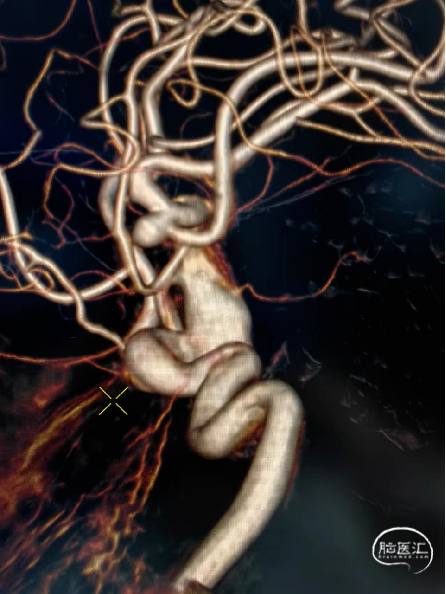

3D重建:

左侧颈内动脉末端夹层动脉瘤、左侧大脑中动脉分叉部动脉瘤、右侧颈内动脉脉络膜前动脉处动脉瘤。

术前测量左侧颈内动脉末端夹层动脉瘤长10mm,瘤体最宽处8mm,载瘤动脉近端血管直径约4.2mm,远端血管直径约3.5mm。拟选用Nuva®血流导向密网支架 TJED-D-4.5-30(预期血管直径长度:4.0mm*40mm)。

沿支架微导管输送Nuva®血流导向密网支架,待支架头端显影点与微导管齐平,支架输送到位,整体回撤微导管和支架至合适的锚定位置,在大脑中M1中段原位释放密网支架。

支架顺利打开,造形可见支架贴壁良好。

1.该病例为多发脑动脉瘤、左侧颈内动脉末端夹层动脉瘤,动脉瘤近远端直径差较大血管迂曲,动脉瘤远端有脉络膜前动脉,传统支架金属填塞弹簧圈有闭塞脉络膜前动脉可能,且复发率较高。很难达到理想的栓塞效果。Nuva®血流导向密网支架操作简便,可以进行原位释放,30%-35%的金属覆盖率起到显著的血流导向作,有利于管腔重建,提高治愈率。